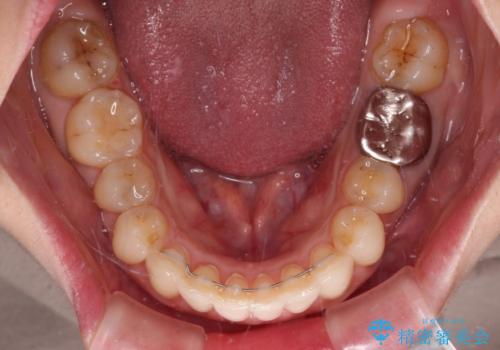

- 上下の前歯のデコボコを気にして来院された患者様です。

妊娠中であり、途中通院が難しくなる可能性があることから、インビザラインによる矯正治療を行うこととしました。

上下顎歯列全体の後方移動とIPR(歯と歯の間を削る)によってデコボコが解消するように設計しました。